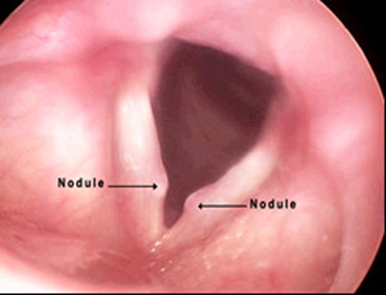

- Polyp dây thanhcó thể xảy ra ở 1/3 giữa dây thanh và thường một bên. Polyps có xu hướng lớn hơn và lồi hơn so với hạt xơ và thường có một mạch máu chiếm ưu thế nên màu hồng nhạt hoặc hồng đậm hơn Chúng thường là kết quả của một thương tích ngữ âm cấp tính khởi phát. Các bệnh tích polyp khác, thường là hai bên, có thể có nhiều nguyên nhân khác, bao gồm trào ngược dạ dày thực quản, bệnh lý suy giáp chưa được điều trị, phản ứng dị ứng thanh quản mạn tính, hoặc hít chất kích thích mãn tính, như khói công nghiệp hoặc khói thuốc. Tổn thương cấp tính thường gây ra các polyp có cuống, trong khi đó viêm phù nề dây thanh là do kích ứng mãn tính.

Hình 2: Polyp dây thanh (T)

- Hạt xơ dây thanh thường xảy ra hai bên ở 1/3 giữa dây thanh. Nguyên nhân chính của chúng là lạm dụng giọng nói mãn tính: la hét, la lớn, hát to, hoặc sử dụng một tần số thấp không tự nhiên.

Hình 3: Hạt xơ dây thanh 2 bên